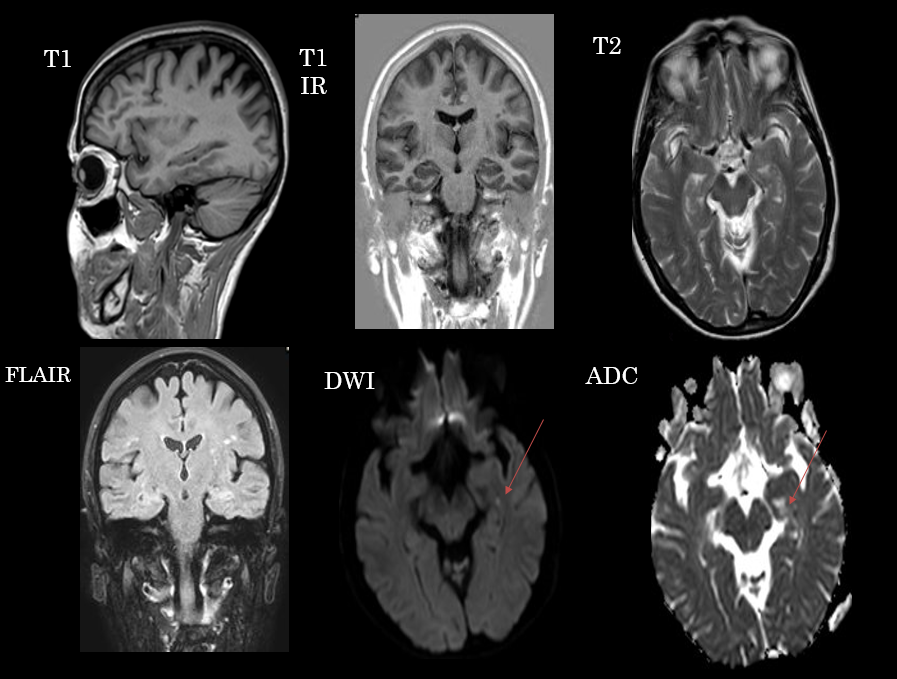

Secuencias de RM sin contraste intravenoso. En difusión se aprecia un foco de restricción puntiforme en hipocampo, que no se manifiesta en otras secuencias.

Lesiones puntiformes en secuencia de difusión en el contexto de amnesia global transitoria.

- Típicamente focos puntiformes que restringen en difusión localizados en hipocampo que suelen ser unilaterales y de predominio en lóbulo temporal izquierdo, aunque pueden ser bilaterales. En ocasiones pueden observarse como lesiones hiperintensas en las secuencias potenciadas en T2. Típicamente suelen desaparecer en control posteriores (>2 semanas).